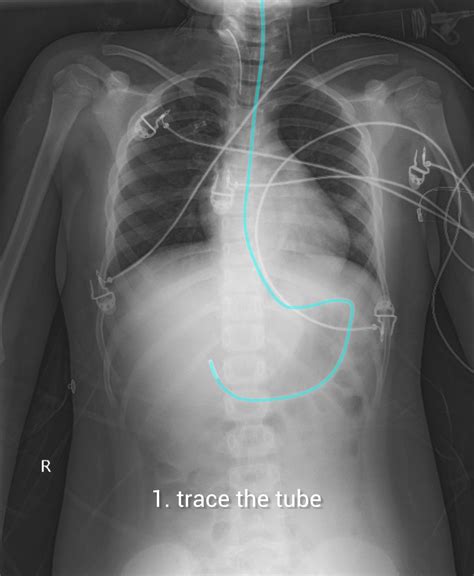

• Tube Advancement: Continue to advance the tube until it reaches the desired location in the small intestine. This can be confirmed using various methods, such as auscultation, pH testing, or X-ray.

• Confirmation of Placement: Use a stethoscope to listen for air insufflation as the tube is advanced. Alternatively, use pH indicator strips to check the pH of the aspirate, which should be alkaline (pH > 6) in the small intestine.

• dobhoff tube placement x ray